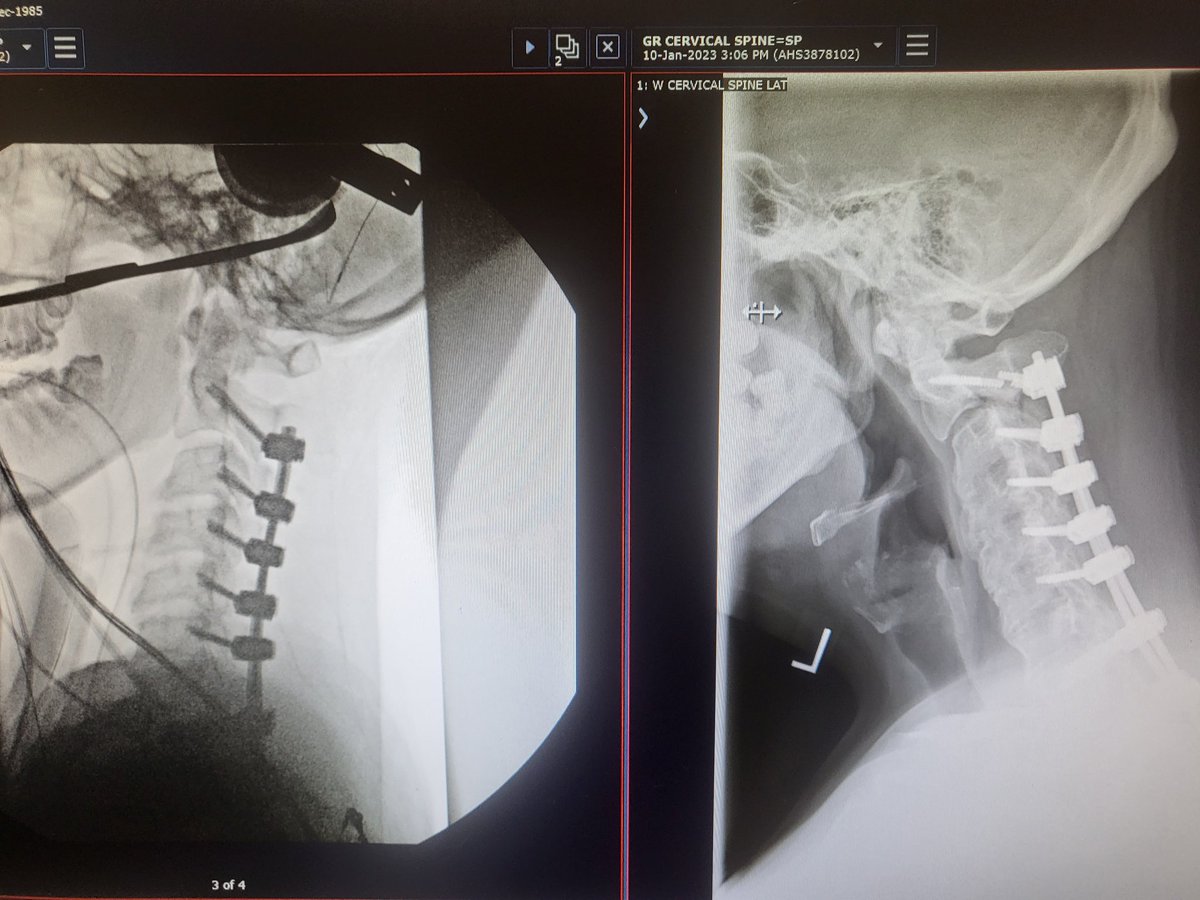

Medical update, since the accident in September, you can see the 2 snapped screws, as well as that section of the vertebrae has shifted forward and is no longer stable. Frustrating part of recovery but we will get through this.